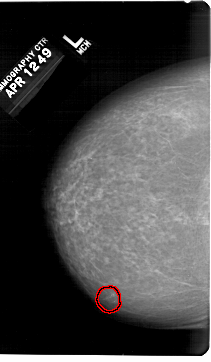

A_1307_1.LEFT_MLO

LEFT_MLO LINES 6751 PIXELS_PER_LINE 4126 BITS_PER_PIXEL 12 RESOLUTION 43.5 OVERLAY

FILE: A_1307_1.LEFT_MLO.OVERLAY

TOTAL_ABNORMALITIES 1

ABNORMALITY 1

LESION_TYPE CALCIFICATION TYPE PLEOMORPHIC DISTRIBUTION CLUSTERED

ASSESSMENT 4

SUBTLETY 4

PATHOLOGY BENIGN

TOTAL_OUTLINES 1

BOUNDARY